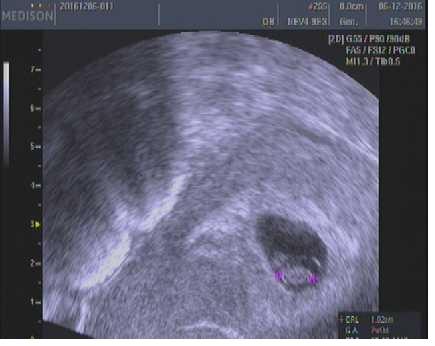

Jinak já jsem po 1. IVF, už 7. den od ET jsem měla //, minulý týden na UTZ potvrzeny dvě bublinky, dneska jsem 5tt+4 a už se do ničeho nevejdu - mám dojem, že s dvojčátkama bude všechno mnohem intenzivnější a rychlejší 😀